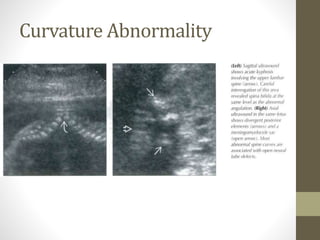

Curvature Abnormality